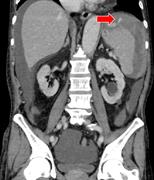

Atraumatic splenic rupture cases presenting with hemorrhagic shock and coagulopathy treated by splenic artery occlusion using a microballoon catheter before splenectomy

Yosuke Matsumura and others

Journal of Surgical Case Reports, Volume 2015, Issue 10, October 2015, rjv121, https://doi.org/10.1093/jscr/rjv121